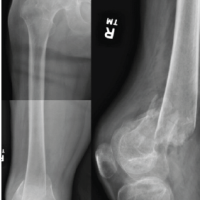

A 30-year-old primigravida at 38 weeks +4 days of gestation presented to the emergency department after a road traffic accident involving a four-wheeler collision. She reported pain and deformity in the left upper limb. The patient had no prior medical comorbidities, and her pregnancy had progressed uneventfully following spontaneous conception. She had adhered to routine antenatal care, including regular intake of iron and calcium supplements, two doses of tetanus vaccination, and standard antenatal screening. She was blood group O-positive and tested negative for Group B Streptococcus. Her menstrual history was unremarkable, with regular cycles occurring every 28–30 days, lasting 3–4 days with average flow. On presentation, the patient was alert, oriented, and hemodynamically stable (blood pressure 100/70 mmHg, heart rate [HR] 98 bpm, RR 18/min, and SpO2 99% on room air via left upper limb). She was afebrile, with no pallor or pedal edema. There was no history of loss of consciousness, ear, nose, throat bleeding, vomiting, or seizures. Local examination of the left upper limb revealed tenderness, swelling, and deformity without any open wounds. Motor and sensory functions were preserved, and radial and ulnar pulses were palpable. Abdominal examination revealed a uterine fundal height consistent with 36 weeks, a longitudinal lie, cephalic presentation, and a tense, rigid uterus. Irregular uterine contractions (2–3/10 min) were noted, along with reduced fetal movements. Cardiotocography (CTG) showed a baseline fetal HR of 175 bpm, with recurrent late decelerations and reduced beat-to-beat variability (<5 bpm). Doppler studies revealed increased umbilical artery resistance (pulsatility index [PI]: 1.48; S/D ratio: 4.2) and a decreased middle cerebral artery PI (PI: 0.82), resulting in a cerebroplacental ratio of 0.55 – indicative of a brain-sparing effect and consistent with intrauterine hypoxia. A non-stress ultrasound showed normal amniotic fluid volume and a singleton fetus in cephalic presentation with no placental or uterine abnormalities. The cervix was 2 cm dilated but closed. Routine laboratory investigations, including complete blood count, coagulation profile, and crossmatch, were within normal limits. Given the gestational age and maternal stability, a trauma protocol was activated involving obstetrics, orthopedics, anesthesiology, and neonatology teams. Plain radiographs of the right arm (with pelvic shielding) revealed a wedge-type diaphyseal fracture of the humerus (AO type 12B2). Closed reduction under traction was performed, and immobilization was achieved with an upper arm (U) slab(Figure 1). Given signs of fetal compromise – possibly due to placental abruption – the multidisciplinary team recommended conservative orthopedic management until delivery.